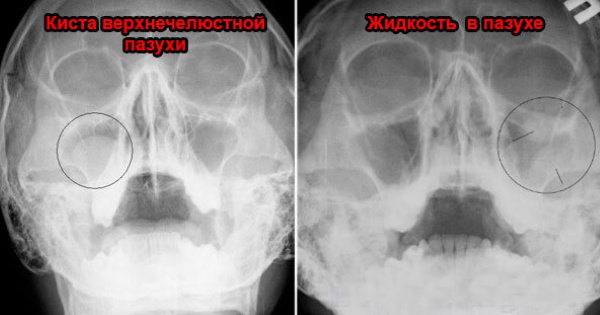

КТ-снимки хронического этмоидита: подробная визуализация